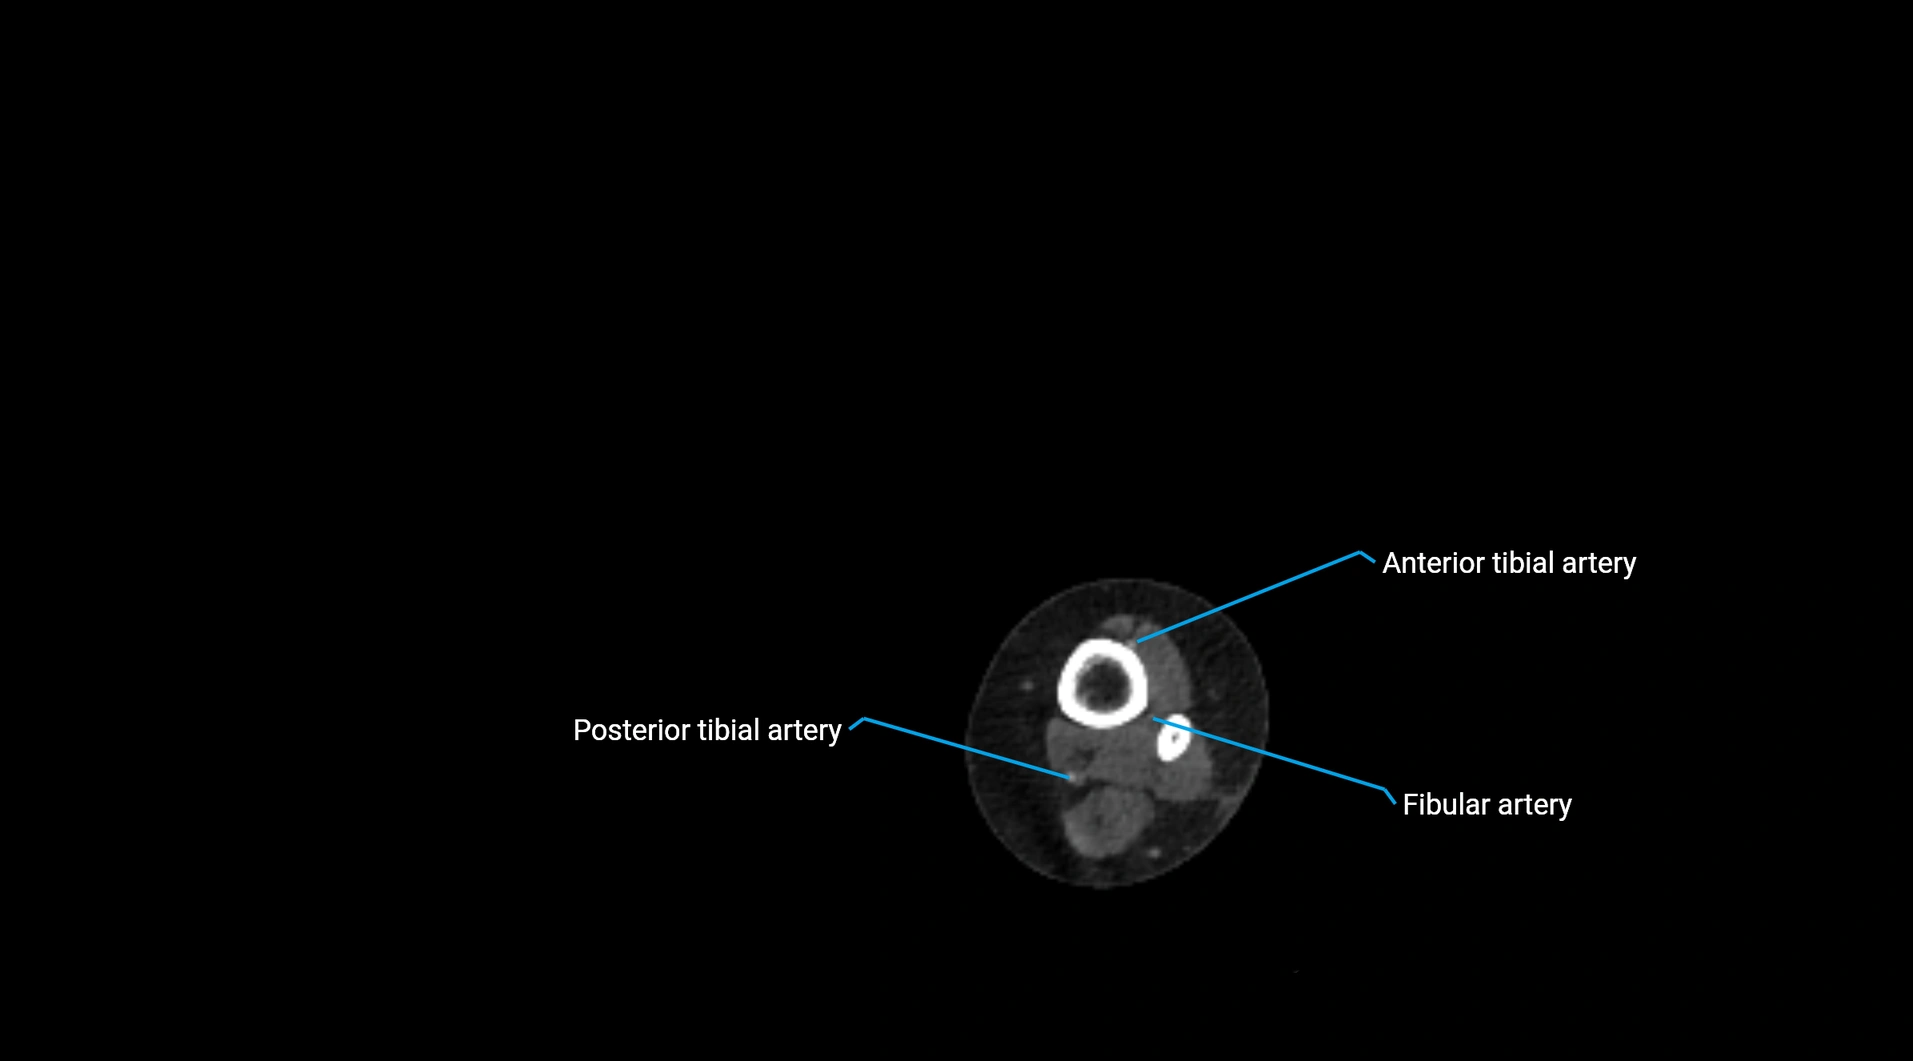

Contrast-enhanced CT (CTA):

• Gold standard for abdominal aortic imaging

• Provides excellent detail of lumen, wall, aneurysm, thrombus, and branch vessels

• Multiplanar and 3D reconstructions help in aneurysm measurement, stent graft planning, and dissection evaluation